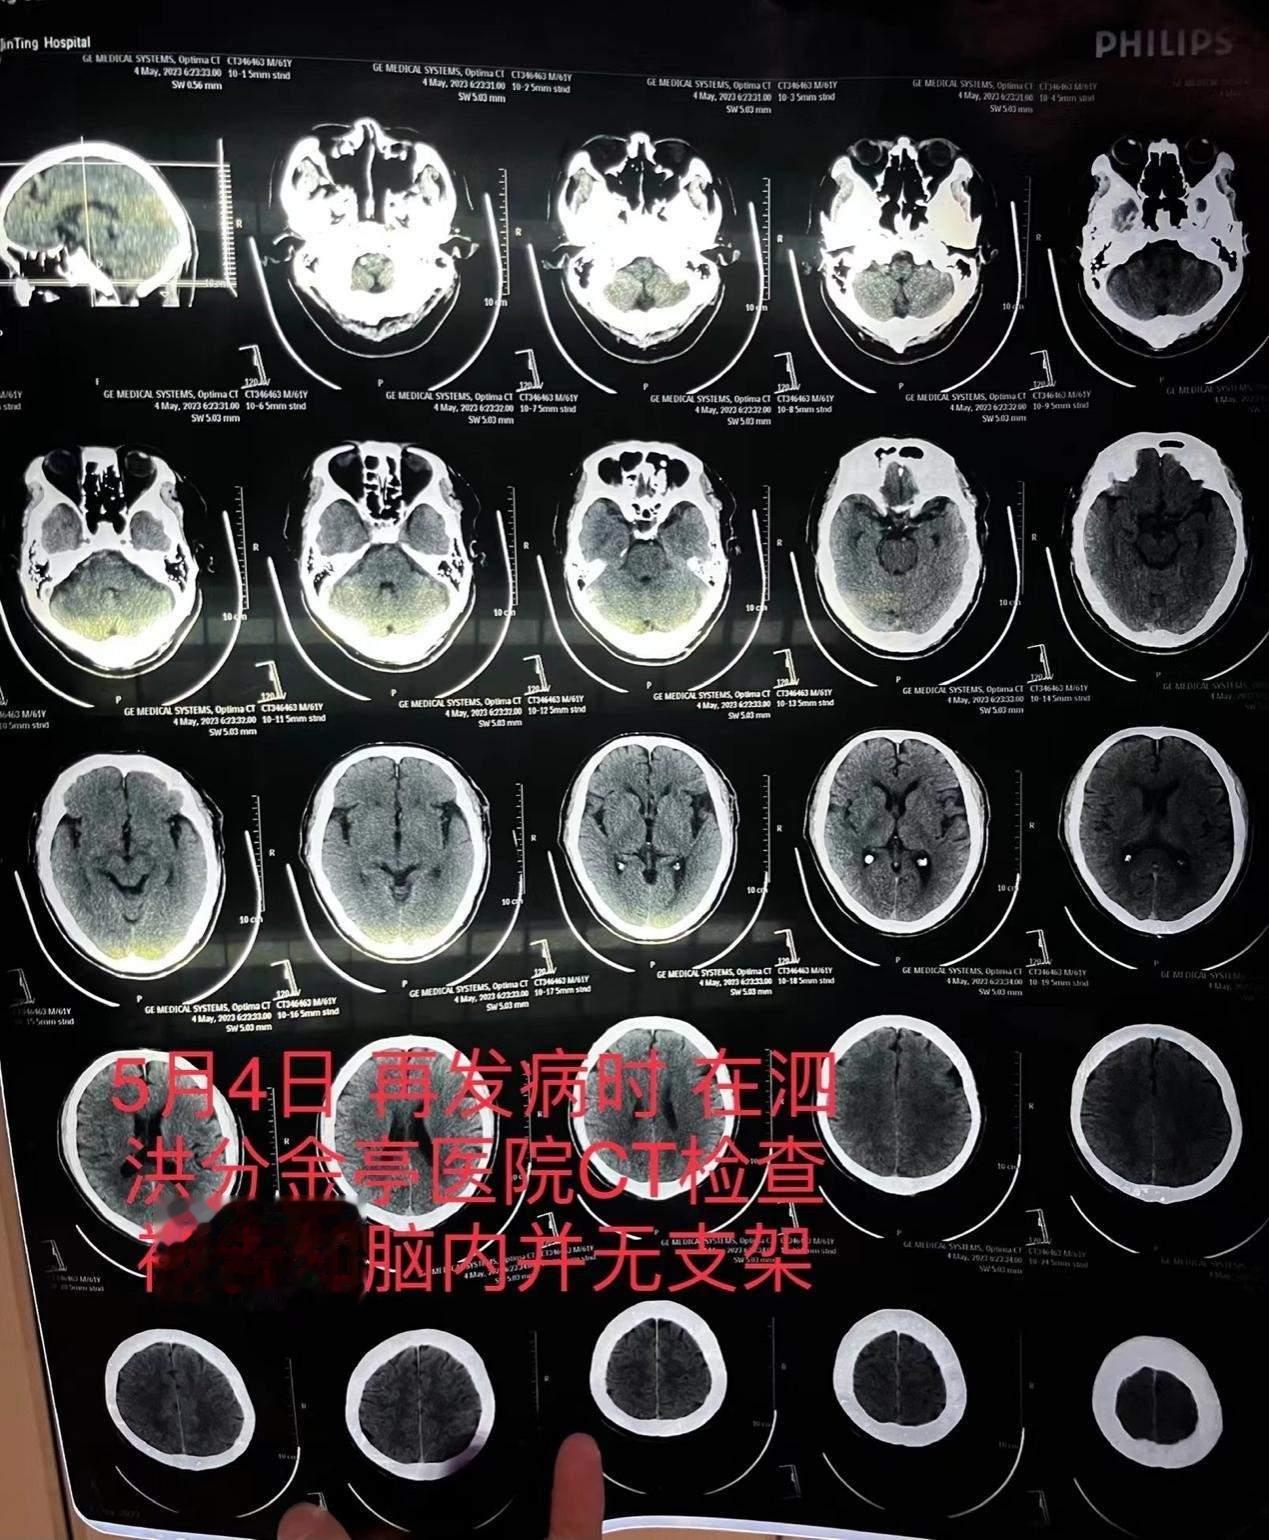

【“消失的脑血管支架”追踪:家属称已妥处,卫健部门未回应】江苏宿迁一位老人脑梗去